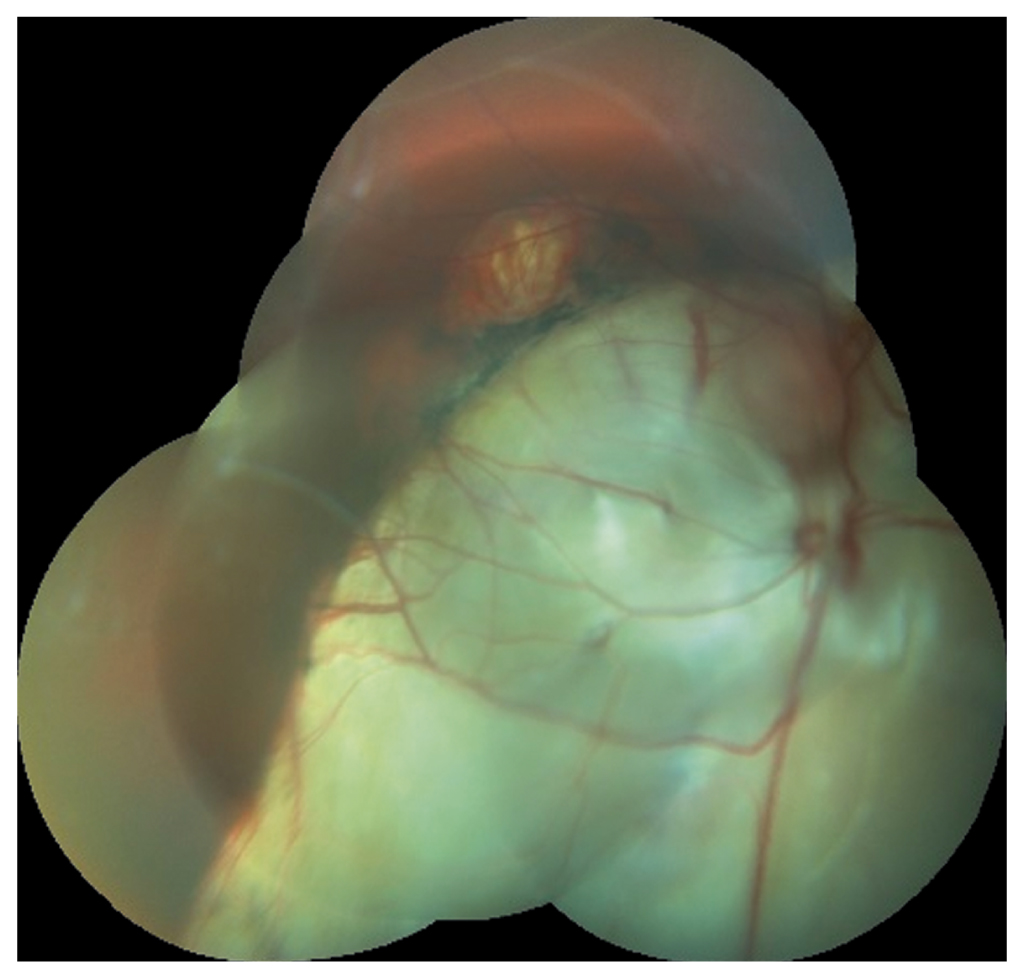

Через 1 сут после операции пациент В. субъективно удовлетворен полученными зрительными функциями на OD. Биомикроскопия OD: роговица каплевидной формы, передняя камера мелкая, влага передней камеры прозрачная, на 6 ч отмечается колобома радужки, эктопия зрачка, ИОЛ в капсульном мешке расположена согласно оси торической разметки ИОЛ, диск зрительного нерва бледно-розовый, границы четкие; колобома диска зрительного нерва. В области нижнего сегмента глазного дна с 5 до 6:30 ч отмечается колобома хориоидеи в виде округлой формы, белого цвета очага без проминенции диаметром 3,5 диска зрительного нерва, тянущегося к центральной части сетчатки с захватом парамакулярной области, что показано на рис. 4. Vis OD=0,6. Пневмотонометрия OD: 16 мм рт.ст.

Рис. 4. Колобома хориоидеи.

Fig. 4. Coloboma of the choroid.